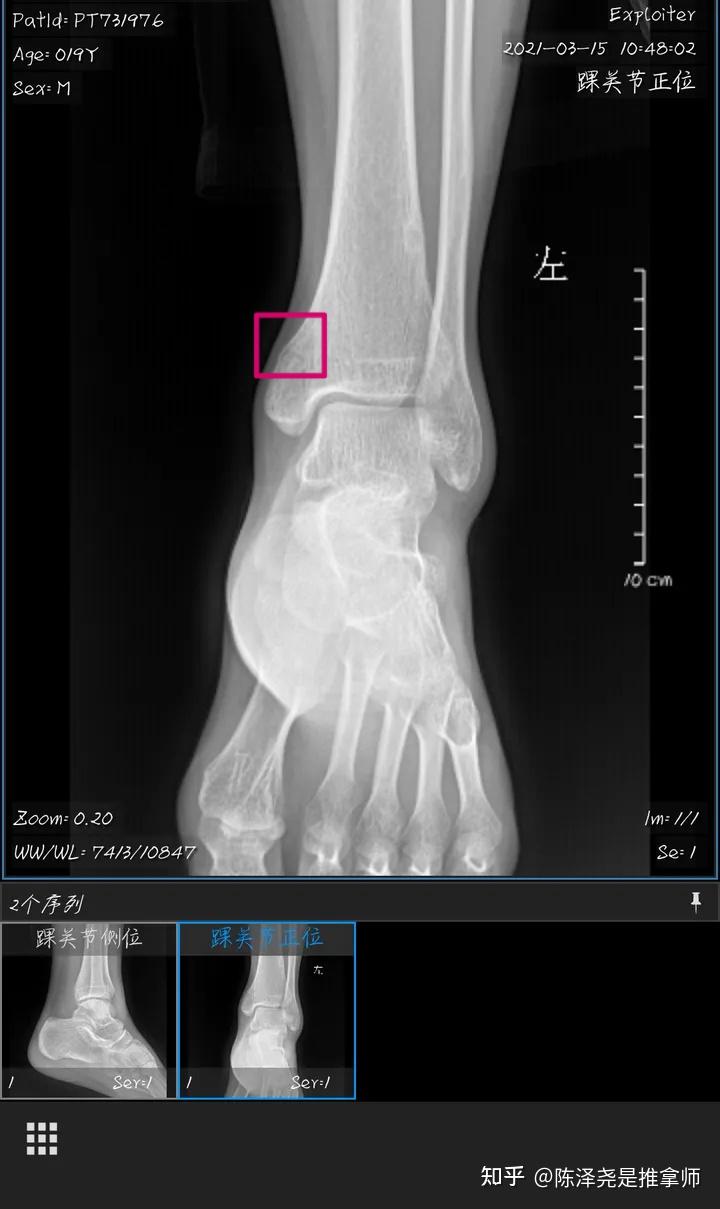

人生第一次骨折左内踝骨折记录一下

我这样是哪里可以给我圈一下吗只知道是坐内踝骨折